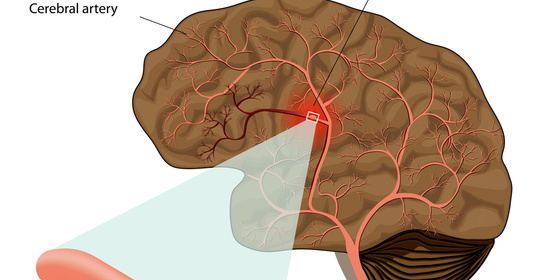

腦出血打嗝是什麼原因

腦出血患者出現打嗝症狀的原因,可能是由於顱內壓升高、膈肌刺激或植物神經受損等原因導致。如果腦出血患者的病情比較嚴重,建議及時送往醫院進行治療。